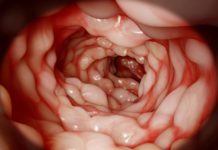

Complex perianal fistulas in Crohn's disease are challenging to treat. Now, the first allogeneic stem cell therapy that...